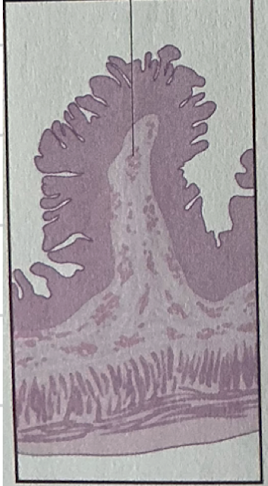

papillae

concentrated on surface of peg-like projections called ______

taste buds

clusters of encapsulated gustatory receptor cells onf surface of tongue